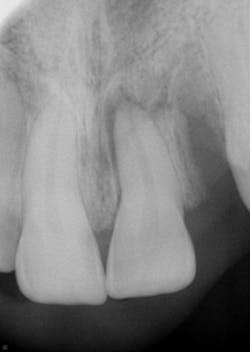

Clinical and radiographic assessment revealed the following (figure 1):

- Complete loss of tooth No. 10 (the patient did not know where the tooth went upon impact).

- Significant swelling in the maxillary and mandibular labial areas with bruising and slight lacerations on the lip and tongue, which were caused when the lower teeth impacted the maxillary teeth with the tongue in between.

- A significant lingual laceration of papilla interproximal to Nos. 8 and 9 with possible involvement of the incisive nerve. Bone exposure was evident.

- Partially avulsed and lingually displaced tooth No. 9 with Class 4 mobility. There was tissue retention only (very light and unstable).

- All other teeth mesial and distal to No. 9 appeared secure.

- Radiographic assessment revealed a horizontal fracture of the alveolar interproximal bone between Nos. 9 and 10 at the apical one-third area. Tooth No. 9 was separated from the alveolar bone with partial avulsion. It was unclear whether the root tip was fractured.

- The patient was unable to bite down due to the mobility and lingual position of No. 9.

Figure 1